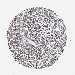

LIVER CANCER - Protein expressioni

A mouse-over function shows sample information and annotation data. Click on an image to view it in a full screen mode. Samples can be filtered based on level of antibody staining by selecting one or several of the following categories: high, medium, low and not detected. The assay and annotation is described here.

Note that samples used for immunohistochemistry by the Human Protein Atlas do not correspond to samples in the TCGA dataset.

Antibody stainingi

Antibody staining in the annotated cell types in the current human tissue is reported as not detected, low, medium, or high, based on conventional immunohistochemistry profiling in selected tissues. This score is based on the combination of the staining intensity and fraction of stained cells.

Each image is clickable and will lead to virtual microscopy that enables deeper exploration of all samples and also displays staining intensity scores, fraction scores and subcellular localization as well as patient and tissue information for each sample.

Antibody HPA021134

Staining

High

Medium

Low

Not detected

Intensity

Strong

Moderate

Weak

Negative

Quantity

>75%

75%-25%

<25%

None

Location

Nuclear

Cytoplasmic/membranous

Cytoplasmic/membranous,nuclear

Cholangiocarcinoma

Carcinoma, Hepatocellular, NOS